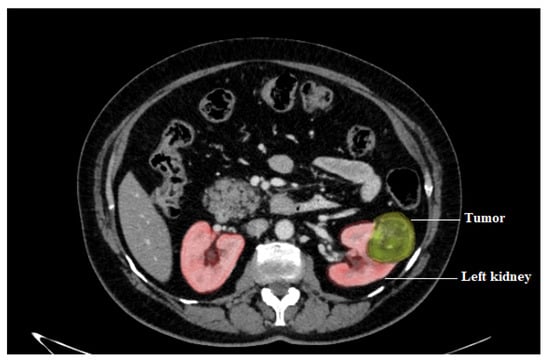

- Computed Tomography (CT): In the kidney areas, widely used to assess the level of RCC. CT scans can help differentiate solid masses from cyst masses and reveal details about the patient’s tumor location, level, and progression to other organs. According to a previous study, tomographic CT imaging features may be used to diagnose patients with RCC by showing cytogenic variations between these cells [19,23,28].